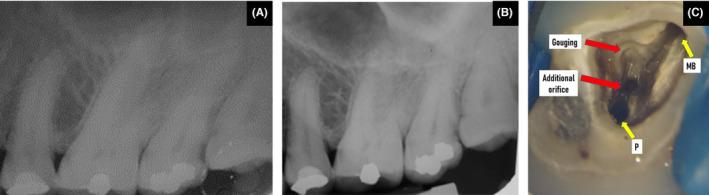

This case report describes the unusual location of the distobuccal root canal in a maxillary second molar with root fusion. On access opening, three distinct root canal orifices, the mesiobuccal canal, palatal canal, and a third orifice closer to the palatal canal, were seen, giving an illusion of an additional palatal canal. An attempt was made to search for the distobuccal canal in its usual position, leading to the gouging of the pulp chamber floor. An intraoperative limited field of view cone-beam computed tomography (CBCT) revealed the root orifice adjacent to the palatal canal was the distobuccal canal. CBCT also revealed fusion of both the buccal and palatal roots in the root's coronal and middle third region, but they were not fused apically.

本病例报告描述了一例上颌第二磨牙牙根融合时远颊根管的异常位置。在开髓时,可见三个明显的根管口,即近颊根管、腭根管以及靠近腭根管的第三个根管口,给人一种额外腭根管的错觉。试图在其通常位置寻找远颊根管,导致髓室底被凿穿。术中有限视野锥形束计算机断层扫描(CBCT)显示,靠近腭根管的根管口是远颊根管。CBCT还显示颊根和腭根在牙根冠部和中部三分之一区域融合,但根尖未融合。